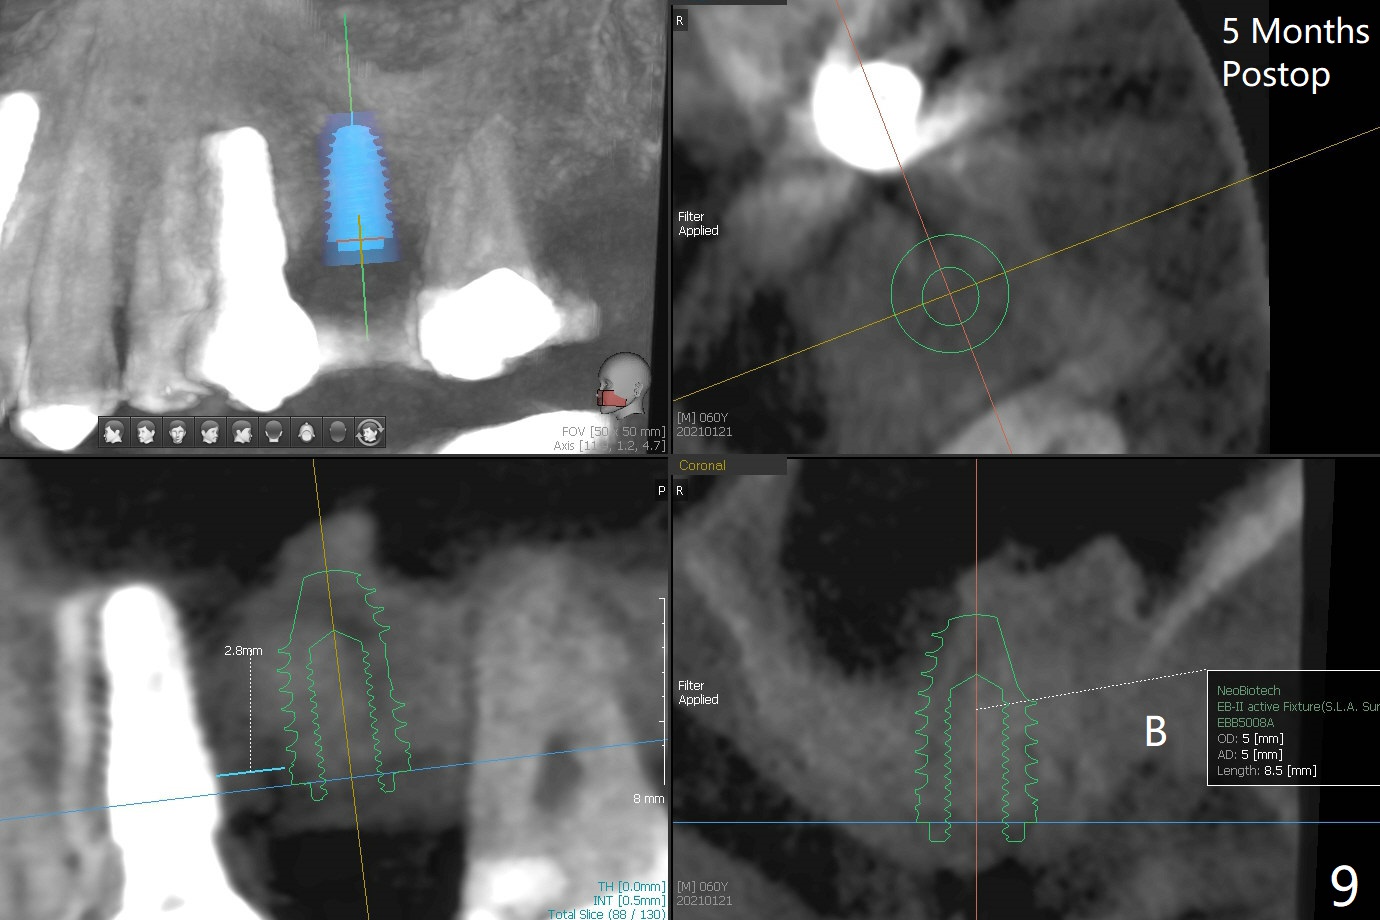

左上六拔除后,近中颊侧窝尤其大,与上颌窦相通(图一 *),而中隔比较尖,截除后还显得窄(图一,二:S),不太适合即刻种植。放置一块PRF膜于近中颊侧窝修补上颌窦,然后放置粘性骨块,好像有上颌窦提升迹象(图三:*(箭头:近中颊侧骨板缺失)),用骨粉填满其余牙槽窝(图四),覆盖另外一块PRF膜以及Cytoplast(不可吸收膜),用PTFE缝线(也不可吸收,与膜是同一个材料,非常柔软,好打结)缝合(图五)。最后使用牙周敷料。后者术后八九天脱落,病人术后十二天复诊,不可吸收膜腭侧有些外翻(图六箭头),伤口愈合尚可,没有骨粉丢失迹象,反复交代口腔卫生。再过三周撤除不可吸收膜。其实三周后膜自己脱落,病人回来撤去剩余缝线(图七),新鲜肉芽组织形成。术后5个月牙槽嵴和角化龈宽,骨高度尚可(图八),密度差些(图九,750单位),植体应该是4.5x8.5 或者 10 毫米,少量上颌窦提升。